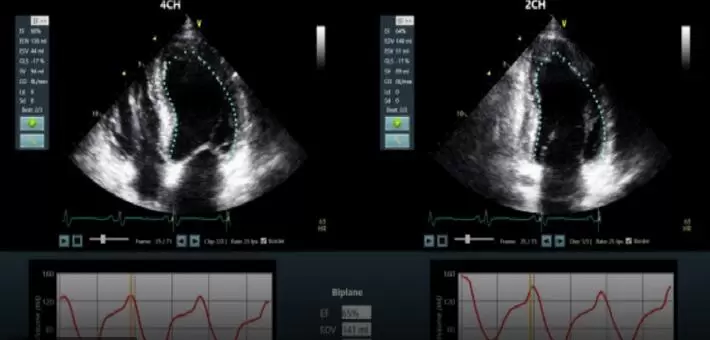

Dia的软件解决方案,是针对小型和手持式超声扫描仪进行优化,借助专有机器的学习算法解决了这些问题。他们可以实时分析扫描和检测的当前模式,模仿人眼识别边界和运动的方式。

该公司的第一款产品用于进行超声心动图检查,并且现已被美国食品药品管理局(the U.S. Food)和欧洲卫生监管机构(Drug Administration and European health regulators)批准了。